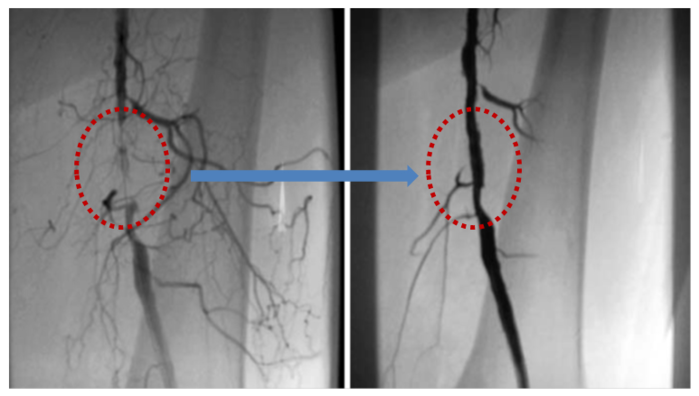

| ▲ 대퇴동맥 시술 사진 |

말초동맥질환은 혈관이 많이 막히지 않은 초기에 발견하면 항혈소판제, 혈관확장제 등 약물치료와 콜레스테롤 관리를 위한 식습관, 생활습관 개선으로 나아질 수 있다. 하지만 증상이 심해 병원을 찾으면 이미 50% 이상 혈관이 막힌 경우가 많다. 막힌 부위가 길어도 수술 위험성이 낮은 경우에는 본인의 정맥이나 인조혈관을 이용해 우회 수술을 진행한다. 그러나 혈관질환 환자는 만성질환을 동반한 경우가 많아 수술로 인한 합병증 가능성이 높아 시술을 고려할 수 있다. 시술은 국소 마취 후 풍선 확장술(혈관에 풍선을 넣고 풍선을 부풀려 혈관을 넓혀주는 시술)이나 스텐트 삽입술(혈관에 그물망 스텐트를 삽입해 좁아지는 것을 방지하는 시술)을 시행한다. 최근에는 죽종절제술(혈관 내벽을 깎아 넓히는 시술) 시행 빈도가 증가하고 있다.